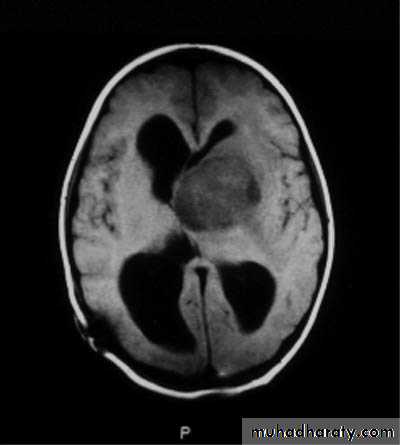

MRIBrain Tumors of Childhood

Histogenesis:* Cell of origin:

glial, neural, primitive, choroid, mixed

* Location:

posterior fossa: 70%

supratentorial: 30%

* Clinical presentation:

location

age

type and grade of the tumor

Symptoms may include:

Increased intracranial pressuresecondary to obstruction of CSF at aqueduct

hydrocephalus (infants), headache, papilledema, vomiting

seizures

focal neurological deficits